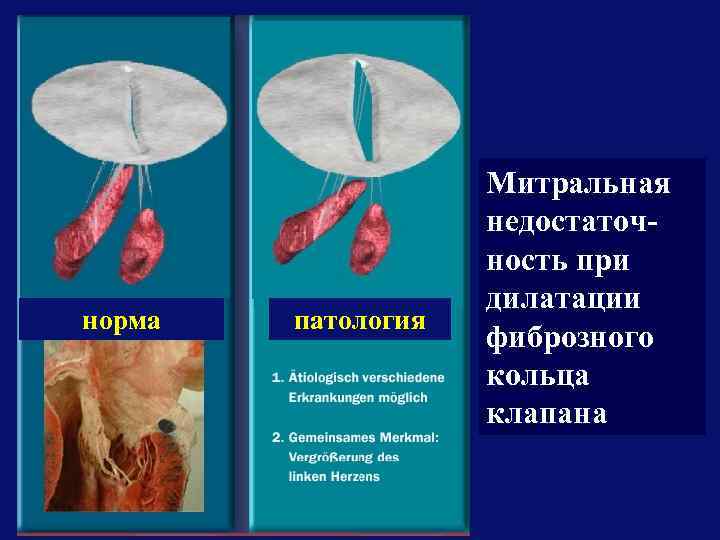

норма патология Митральная недостаточность при дилатации фиброзного кольца клапана